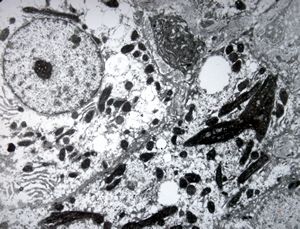

M,66y. | siderosomes

M,66y. | hemosiderin - siderosomes